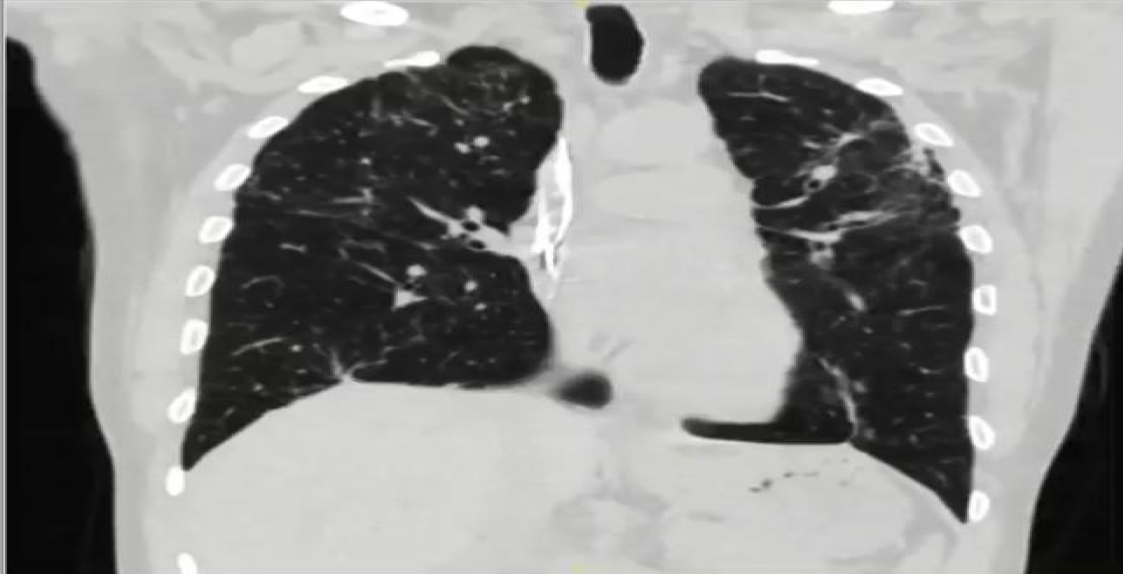

Telemetry showed a high premature ventricular complex (PVC) burden coupled with episodes of non-sustained ventricular tachycardia (NSVT). Electrocardiogram (ECG) showed frequent PVCs (Figure 2). Chest X-ray showed coarse reticulonodular infiltrates with diffuse lung nodules and bronchial wall thickening. Computed tomography angiogram (CTA) of the chest (Figure 3) demonstrated diffuse pulmonary nodules in all lung lobes and dilated main pulmonary trunk consistent with pulmonary hypertension.